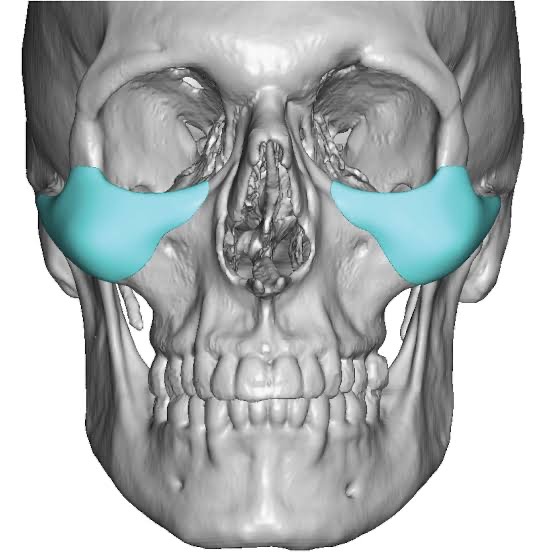

@anthony111553 Wdyt about male cheekbones

just searched them up@anthony111553 Wdyt about male cheekbones

@yussimania Is it an issue for these to cause a wider midface? Also they seem to benefit women more than men

@yussimania Is it an issue for these to cause a wider midface? Also they seem to benefit women more than men

@yussimania Is it an issue for these to cause a wider midface? Also they seem to benefit women more than men

A wider face/ midface rlly isn’t bad at all it’s when it’s combined with a compact midface ratio is when it starts to look like dog shitIs it an issue for these to cause a wider midface? Also they seem to benefit women more than men

How shit zygos im nglA wider face/ midface rlly isn’t bad at all it’s when it’s combined with a compact midface ratio is when it starts to look like dog shit

Either way though I wouldn’t get it unless u have rlly shit zygos

Like rlly shitHow shit zygos im ngl

@yussimania Is it an issue for these to cause a wider midface? Also they seem to benefit women more than men

if your jaw is larger than your cheekbones go for it but be wary it affects your eye separation ratioView attachment 4278369

@yussimania Is it an issue for these to cause a wider midface? Also they seem to benefit women more than men